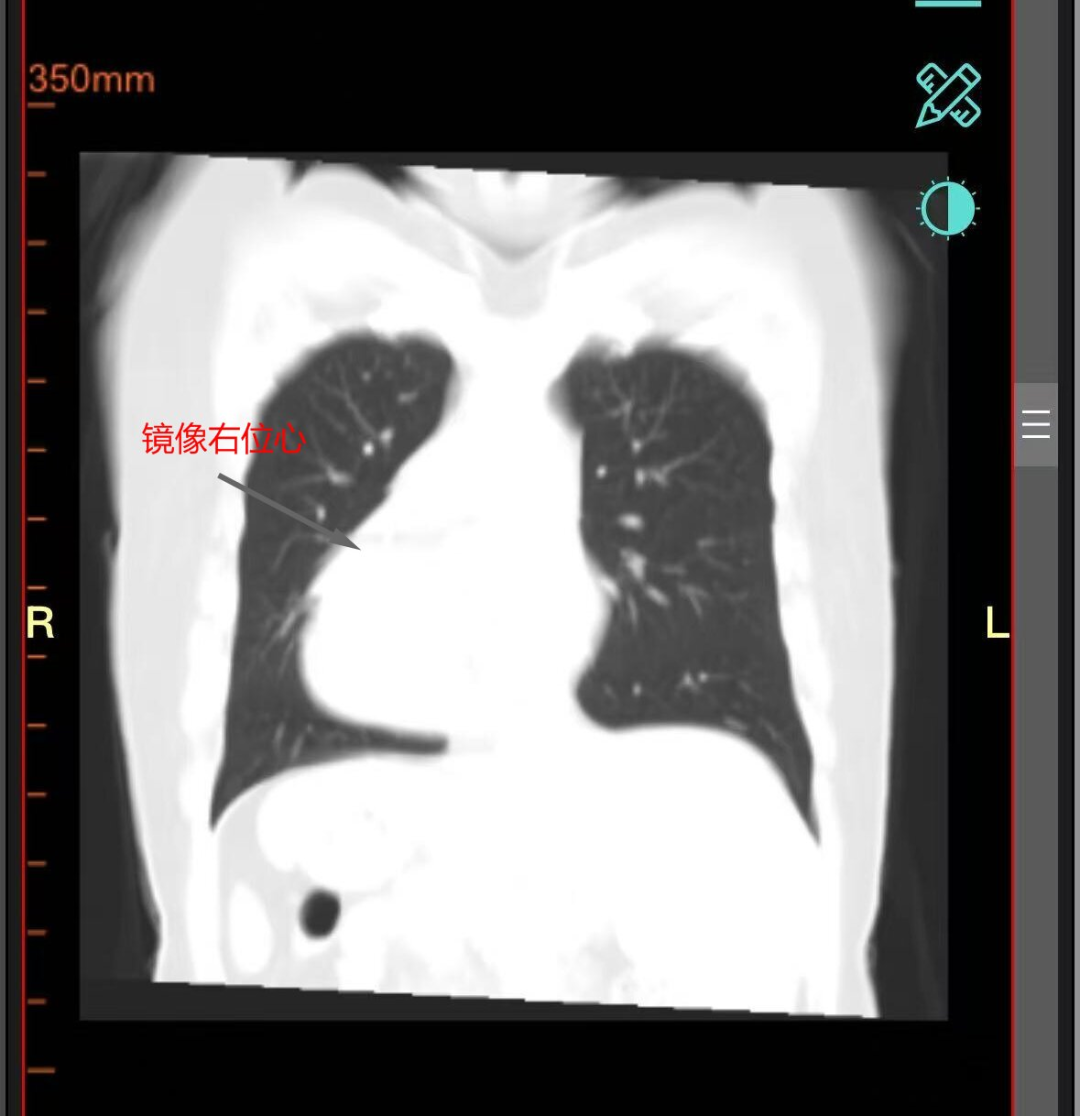

32岁的王女士近两年反复上腹疼痛,到岳阳市中医医院检查后得知困扰她的正是胆囊结石合并胆囊炎。这本是一个外科常见病,但入院前王女士体检显示,王女士是一名全内脏反位患者。简单来说就是她的心脏、肝脏、胃、胆囊等所有胸腔腹腔器官的位置,与正常人完全相反,如同镜中影像。对一般人来说,胆囊切除是个常规手术,但对王女士而言,却变得异常复杂——因为她的胆囊不在右边,而在左边。这无疑大大增加了诊断的复杂性和手术的风险与难度,许多医院对此类手术倍感棘手。

首先,医学影像科为王女士做了详细CT和MRI检查,将王女士的“镜面”内脏绘制了一幅极其精确的“倒置地图”,清晰展现了反位器官的形态、血管走行、胆道结构关系,为手术路径提供了至关重要的导航。